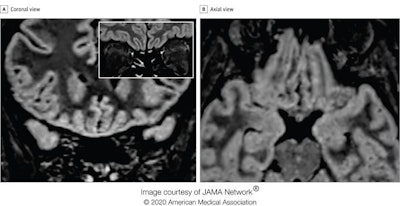

MRI scans of a 25-year-old Italian radiographer who contracted COVID-19 and lost her sense of smell suggest the virus may invade the brain through the olfactory pathway and cause dysfunction of sensorineural origin. This finding was published online by JAMA Neurology on 29 May.

"To our knowledge, this is the first report of in vivo human brain involvement in a patient with COVID-19 showing a signal alteration compatible with viral brain invasion in a cortical region (i.e., posterior gyrus rectus) that is associated with olfaction," noted Dr. Letterio Politi and colleagues from the department of neuroradiology at the Scientific Institute for Research, Hospitalization, and Health Care (IRCCS) Humanitas Research Center, Milan. "Alternative diagnoses (e.g., status epilepticus, posterior reversible encephalopathy syndrome-like alterations, other viral infections, and anti-N-methyl-D-aspartate receptor encephalitis) are unlikely given the clinical context."

The researchers performed two MRI exams on a 1.5-tesla scanner using a 20-channel phased-array head/neck coil. They used no contrast agent and acquired 2D and 3D FLAIR, T2-weighted turbo spin-echo, T1-weighted spin-echo, and high-resolution diffusion-weighted images, Constructive interference in steady-state and susceptibility-weighted imaging sequences were employed.

In follow-up MRI performed 28 days later, the signal alteration in the cortex had completely disappeared and the olfactory bulbs were thinner and slightly less hyperintense. The patient had recovered from anosmia. On 6 May, a blood sample was positive for the immunoglobulin G antibodies against the SARS-CoV-2 virus.